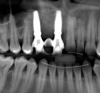

Tomographic images revealed a large tridimensional defect, with vertical and horizontal loss of bone extending to the apical third of teeth Nos. 6 and 8. Additionally, a buccal bone dehiscence was evident on tooth No. 5, and thin labial plates secondary to the orthodontic movement were present in several areas (Figure 3 and Figure 4).

Fig 3. Tomographic images revealed a tridimensional defect extending to the apical third of teeth Nos. 6 and 8, a buccal bone dehiscence on tooth No. 5, and associated thin labial plates.

Figure 3